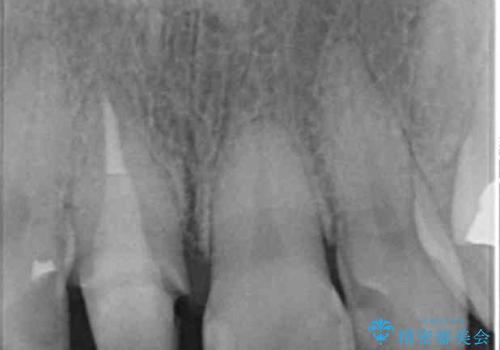

折れてしまった前歯 オールセラミックによる審美改善

- 「野菜をかじった際に前歯がぐらつき、その場で取れてしまった。前歯を入れたい。」と希望され来院されました。

残っている歯質(歯の量)は非常に少ないものの、歯を抜かずに残したい希望が強く、また破折リスクが高いことも

ご理解いただいた上で歯を残しセラミック治療を計画します。

破折リスクを少なくするため前歯でかじったり硬いものを噛み切る等の行為は避けた方が良いとお伝えし、現状5年問題なく経過しています。